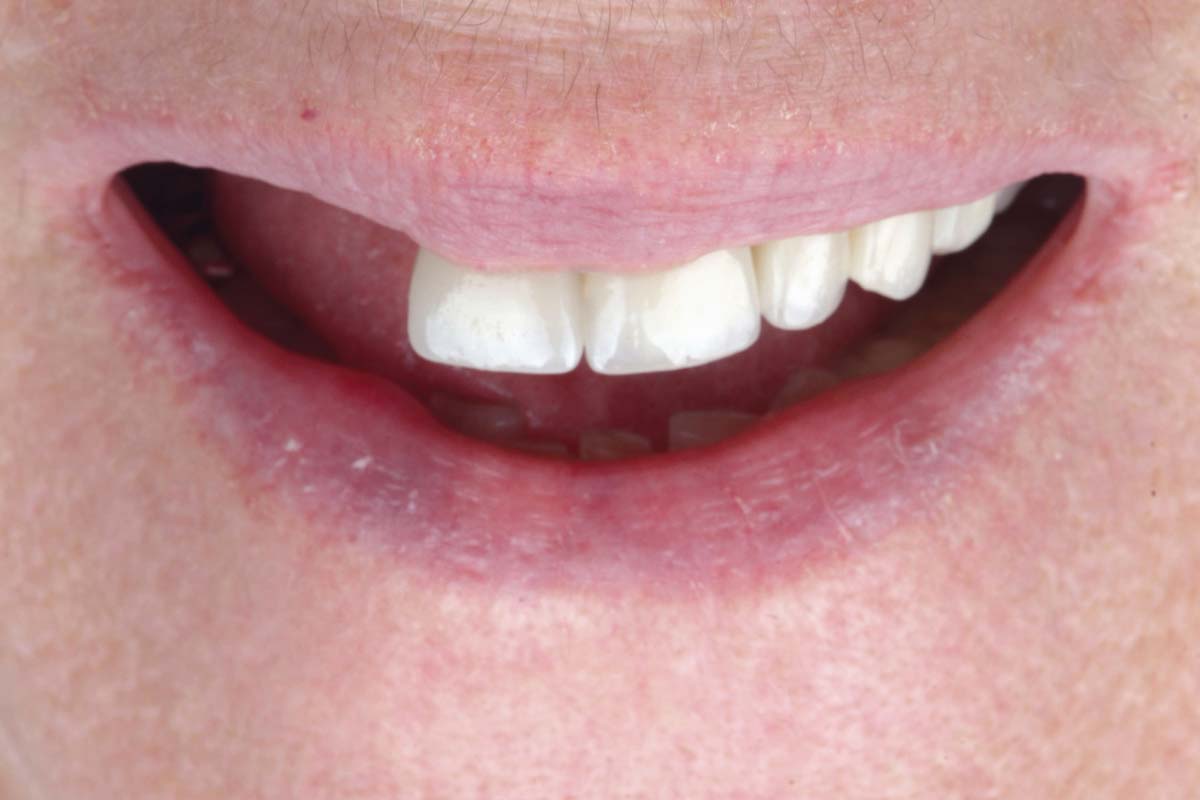

Loss of teeth in anterior maxilla caused by periodontitis